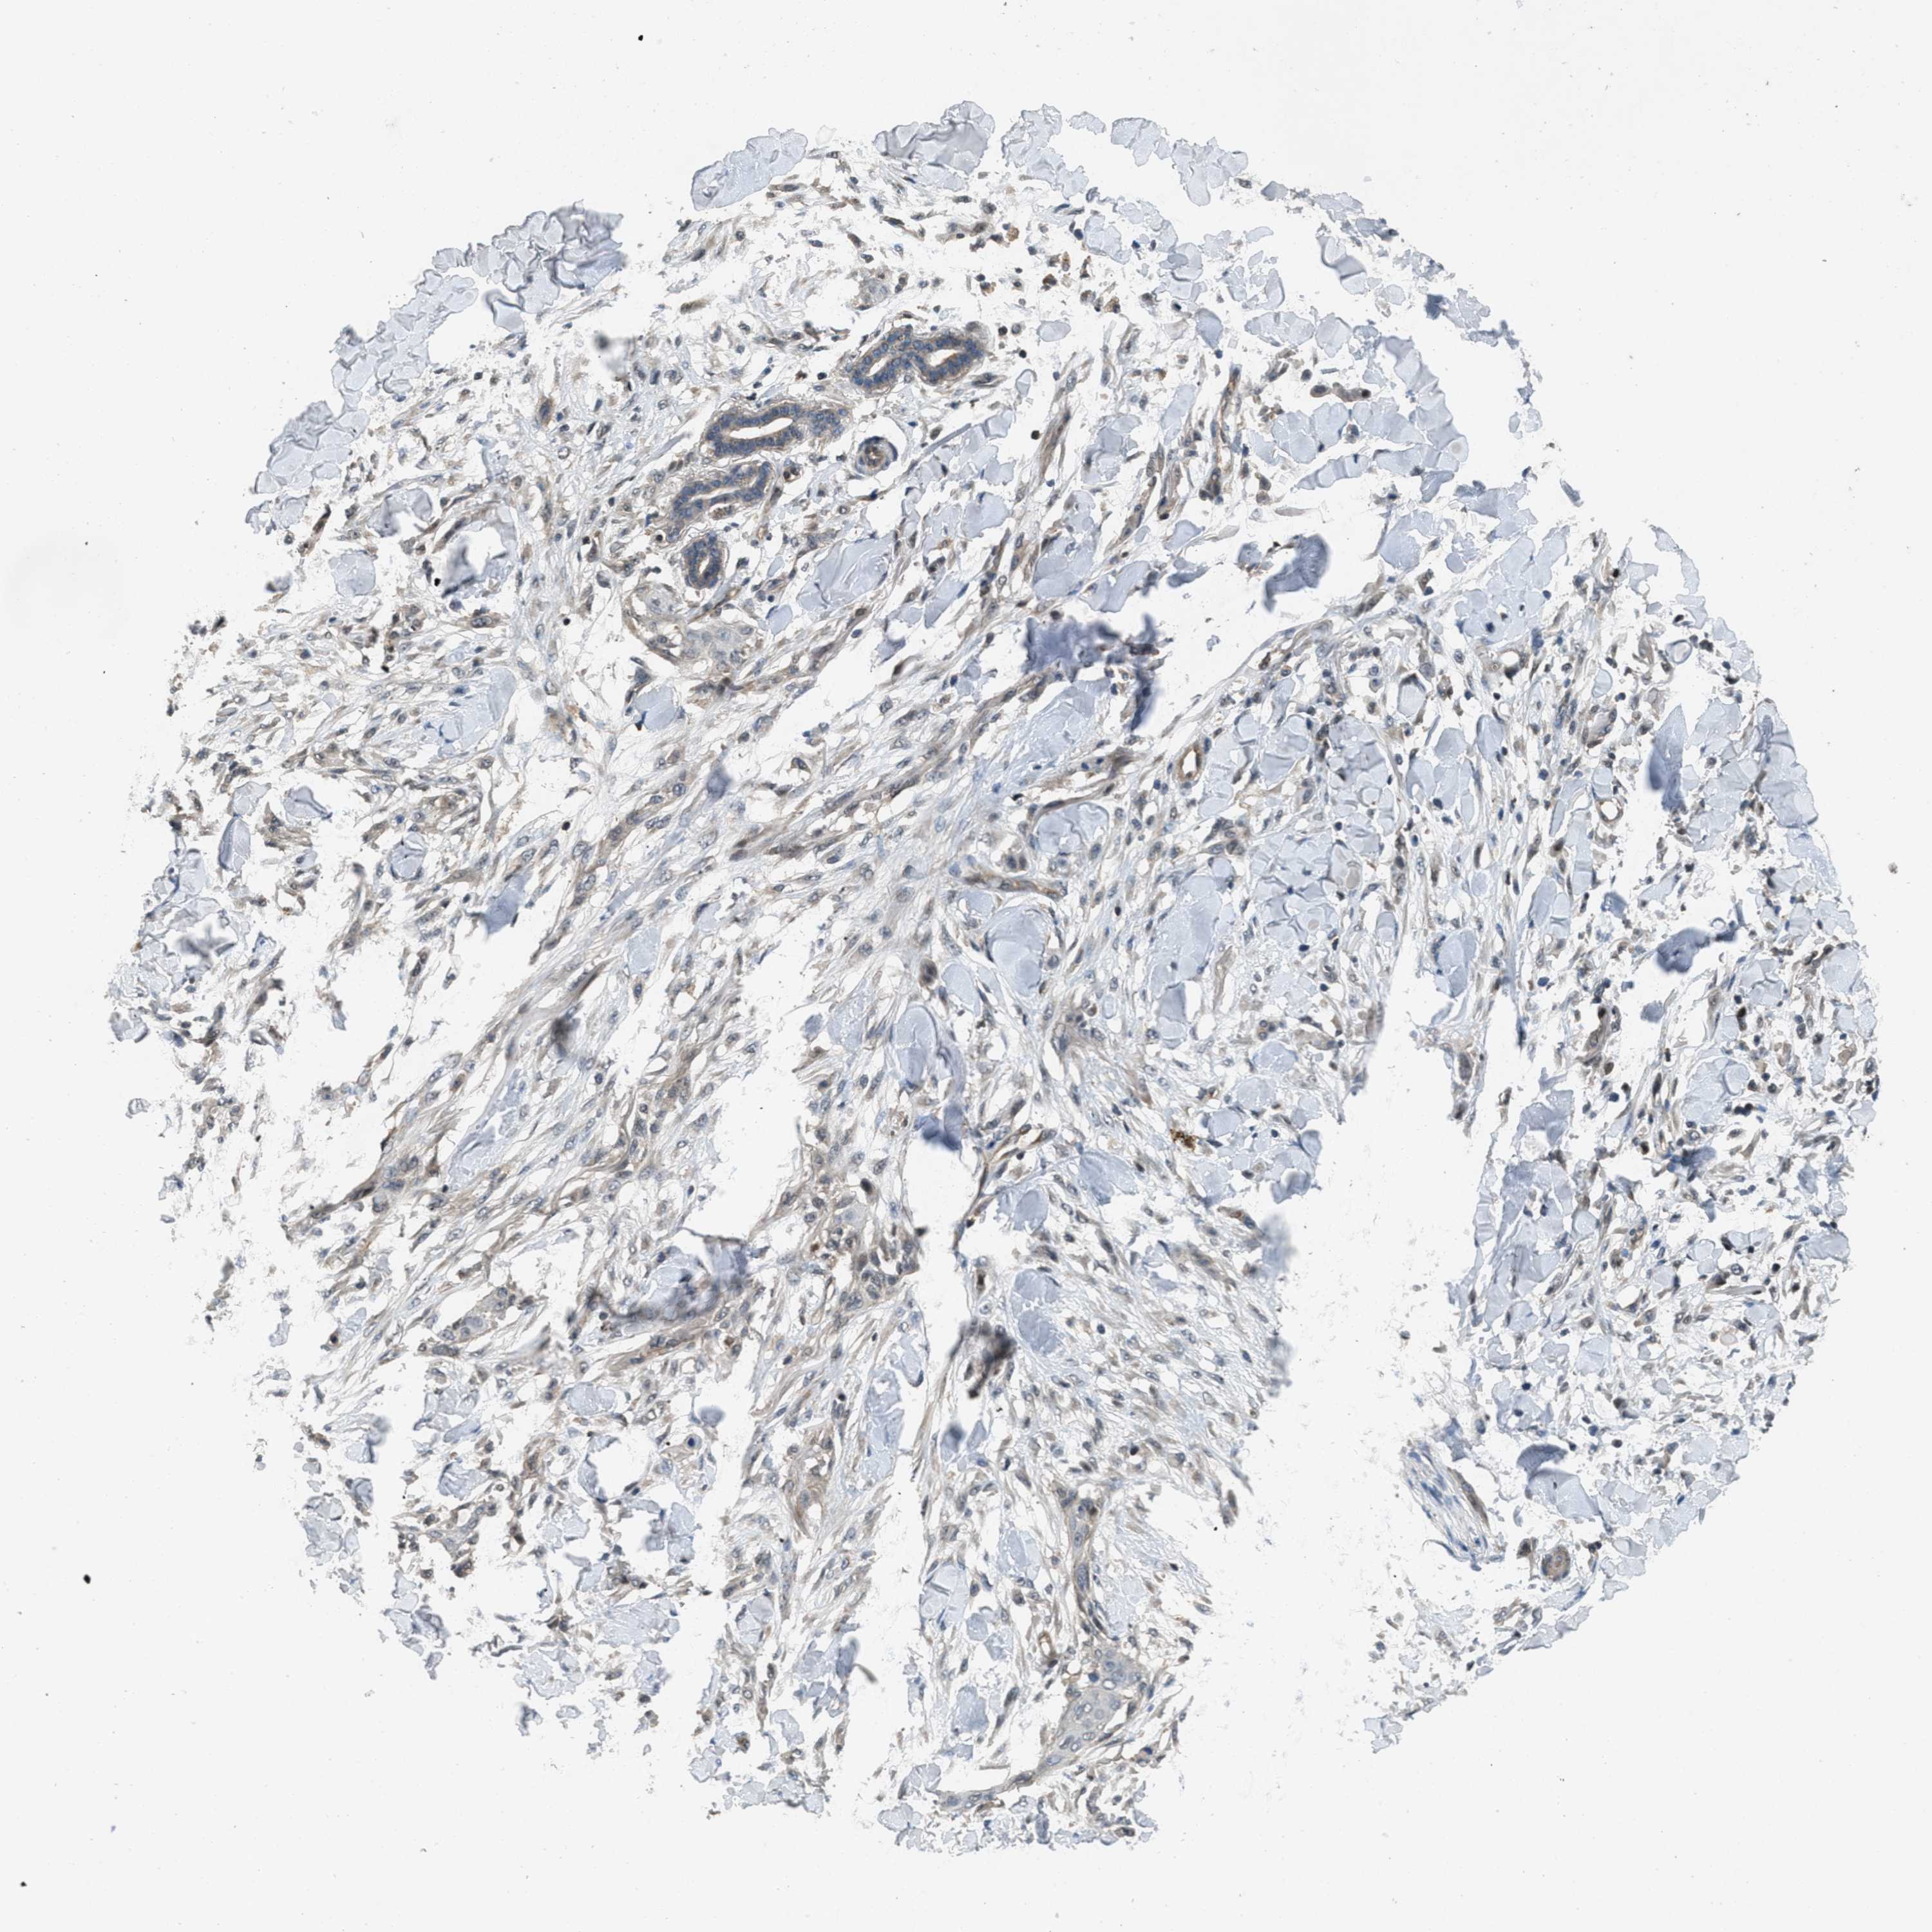

SKIN CANCER - Protein expressioni

A mouse-over function shows sample information and annotation data. Click on an image to view it in a full screen mode. Samples can be filtered based on level of antibody staining by selecting one or several of the following categories: high, medium, low and not detected. The assay and annotation is described here.

Each image is clickable and will lead to virtual microscopy that enables deeper exploration of all samples and also displays staining intensity scores, fraction scores and subcellular localization as well as patient and tissue information for each sample.

Antibody CAB017566

Staining

Low

Intensity

Weak

Quantity

<25%

Location

Cytoplasmic/membranous,nuclear

Basal cell carcinoma